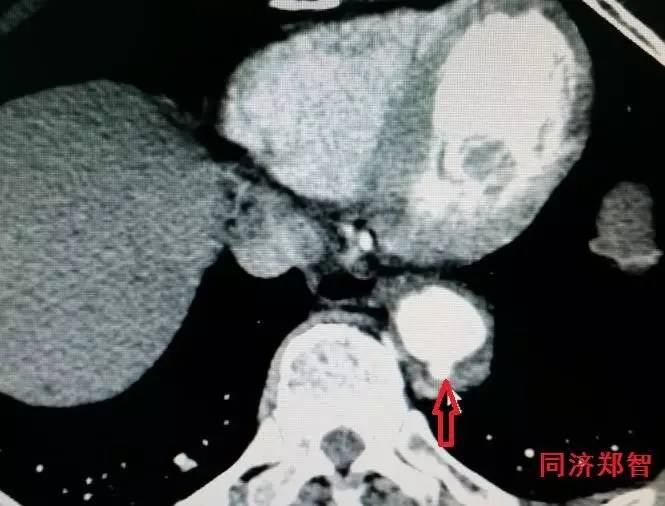

有时候平扫CT也能从血管内密度影的不同来诊断主动脉壁间血肿(图3)。平扫CT提示右肺动脉层面的升主动脉外侧为新月状稍亮的影(红箭头所示)。

图3

CT增强后证实为升主动脉壁间血肿(图4),如红箭头所示。

图4